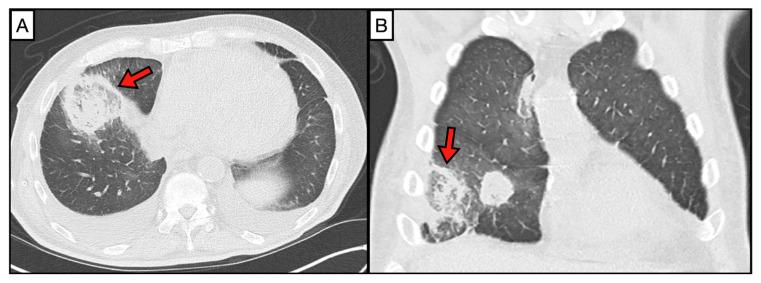

Mucormycosis, an invasive fungal infection caused by members of the order Mucorales, often progresses fulminantly if not recognized in a timely manner. This comprehensive review discusses the latest developments in diagnostic approaches for mucormycosis, from traditional histopathology and culture-based methods to advanced and emerging techniques such as molecular assays, imaging, serology, and metabolomics. We discuss challenges in the diagnosis of mucormycosis and emphasize the importance of rapid and accurate identification of this life-threatening infection.

毛霉病是一种由毛霉目真菌引起的侵袭性真菌感染,如果不能及时识别,通常会迅速发展。这篇综述讨论了毛霉病诊断方法的最新进展,从传统的组织病理学和基于培养的方法到先进的新兴技术,如分子检测、影像学、血清学和代谢组学。我们讨论了毛霉病诊断中的挑战,并强调了快速准确识别这种危及生命的感染的重要性。